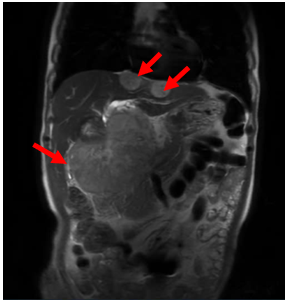

- Cộng hưởng từ ổ bụng: Nhu mô gan 2 bên có vài khối nốt tổn thương, lớn nhất vị trí rốn gan kích thước 105x140x132mm, bờ không đều, giảm tín hiệu trên T1W, có phần tăng tín hiệu trên T1W dạng chảy máu, tăng nhẹ không đồng nhất trên T2W, hạn chế khuếch tán trên DWI/ADC, sau tiêm ngấm thuốc ở ngoai vi thì động mạch, ngấm thuốc lan dần vào trung tâm thì muộn, thì gan mật không giữ thuốc. Tổn thương xâm lấn đè đẩy hạn chế đánh giá nhánh trái TMC, đè đẩy hẹp thân chung TMC

Hình ảnh chụp Cộng hưởng từ có tiêm thuốc đối quang từ (T1W): Vị trí các khối u theo hướng chỉ của mũi tên đỏ